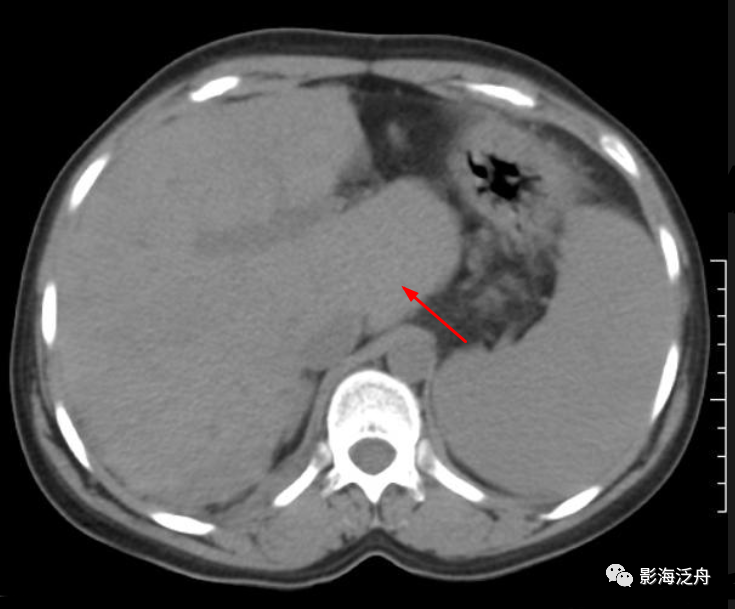

早期布加综合征患者(30岁女性),肝尾状叶(CL)体积明显增大,其余肝实质轮廓尚可,但强化程度明显减低,呈散在斑片状强化(白箭),系肝淤血所致,腹腔可见积液(星号),三角所指为非受累节段的下腔静脉。肝尾状叶可以在布加综合征中做到“独善其身”,完全是拜其独特的解剖结构所赐。多数肝硬化患者也可以看到尾状叶增大。